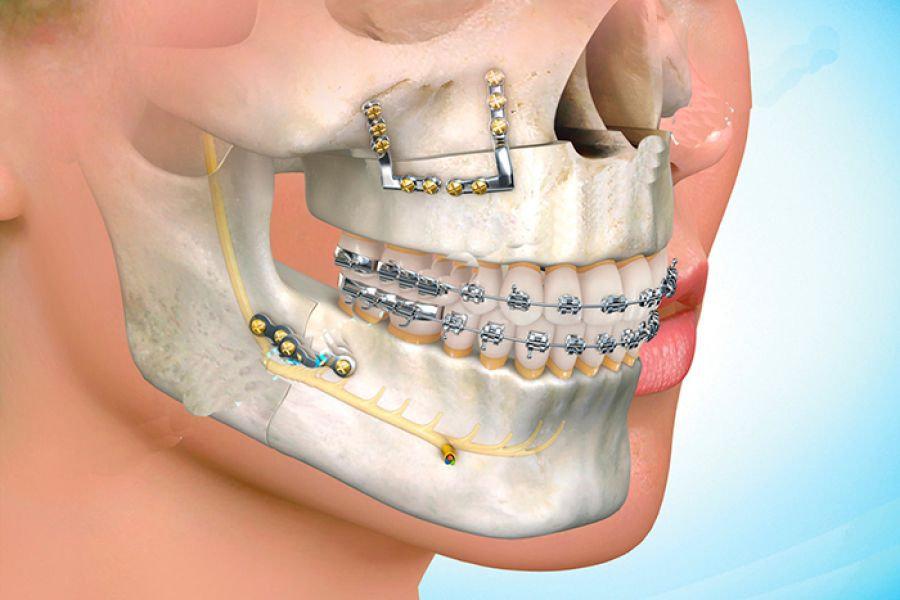

Dental implants

Our dental implant service is designed to permanently and naturally replace missing teeth, using the latest global implant systems to ensure high stability, aesthetic appearance, and excellent function.

We offer comprehensive solutions, starting with accurate diagnosis, through the implant procedure, and culminating in the placement of the final crown, for a stable and comfortable smile that lasts for years.